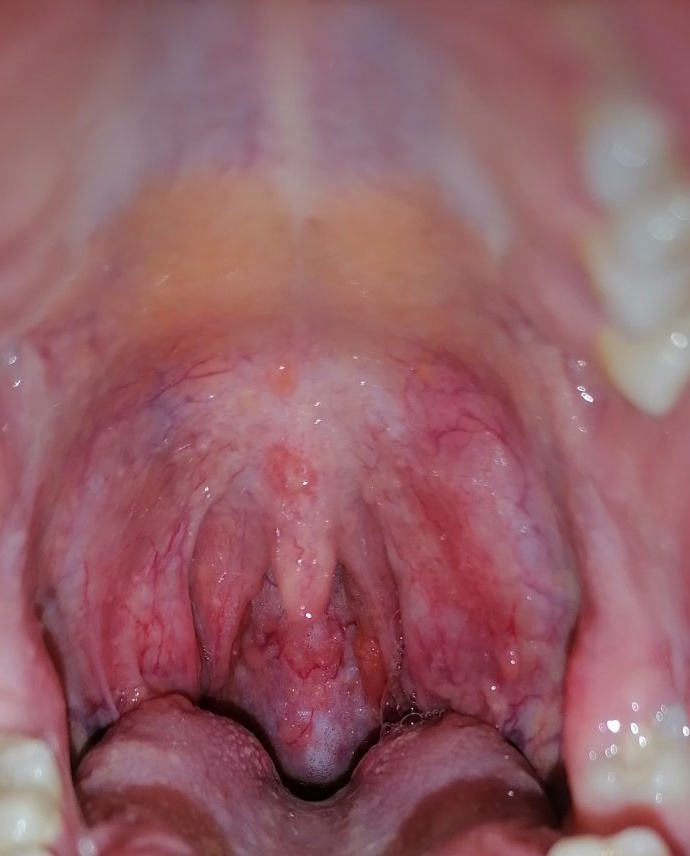

nemyslím si, že máte angínu, hrdlo je začervenané, najskôr pôjde o nejakú virózu.

Skúste kloktať slabú vodu alebo Tantum verde alebo Glimbax, ak by sa ťažkosti nezmiernili, tak sa poraďte s Vašim lekárom.